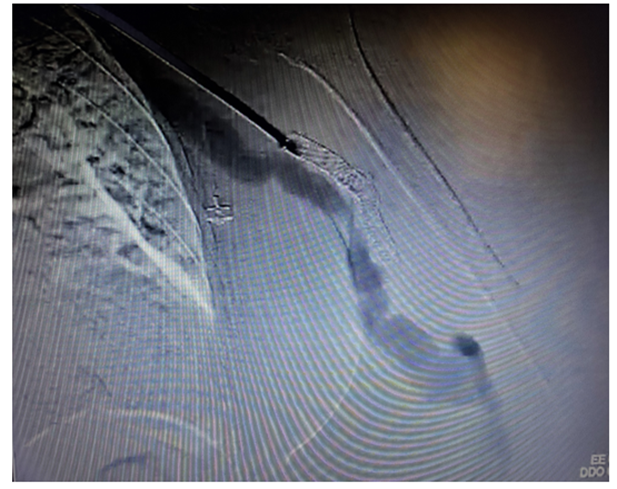

The patient was urgently submitted to an endovascular treatment of the AVF and brachial artery acute thrombosis. Under general anesthesia, a left common femoral artery was retrograde punctured guided with a duplex ultrasound to perform the whole intervention percutaneously with a proper sheat. Then, upper left arm arteriography showed: brachial artery occlusion immediately before stenting, with brachial artery refilling before anastomosis focal venous stenoses. (Figures 1 and 2).

Figure 1: Intraoperative image showing brachial-basilic arteriovenous fistula and a Viabahn occlusion